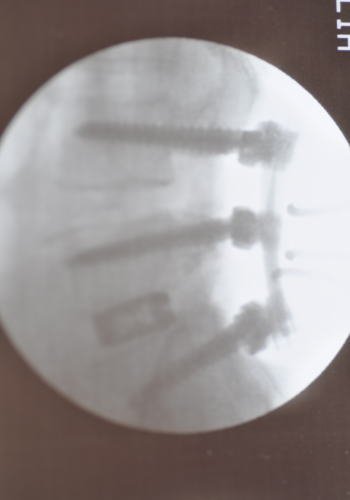

トップ画像が悪の根源、椎間板。

ひえ~!なんか・・・生々しい・・・(汗)

そして写真も見せられた。

これは横から撮ったもの。

ボルトがしっかり入ってます。

下のほうの四角いのもチタンのプレート。

トップ画像が悪の根源、椎間板。

ひえ~!なんか・・・生々しい・・・(汗)

そして写真も見せられた。

これは横から撮ったもの。

ボルトがしっかり入ってます。

下のほうの四角いのもチタンのプレート。